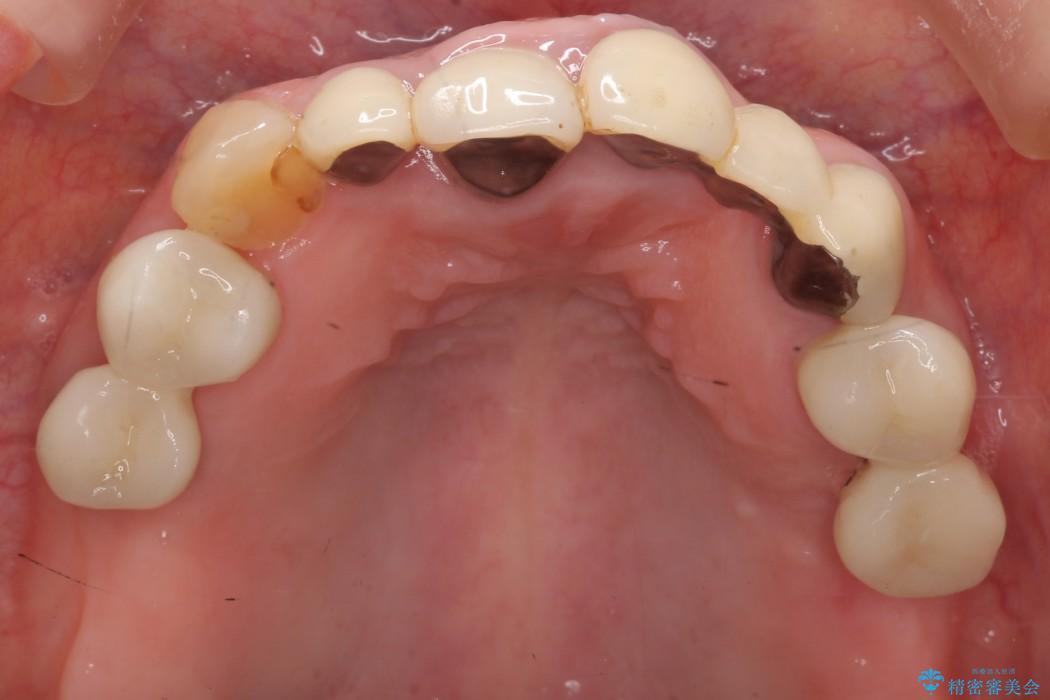

メタルフリー治療

その名の通り金属を使用しない治療です。

今回の症例では金属の色が透けていることを気にされていたので、土台から金属を除去し、金属を使用していないオールセラミックのかぶせ物を使用することとしました。